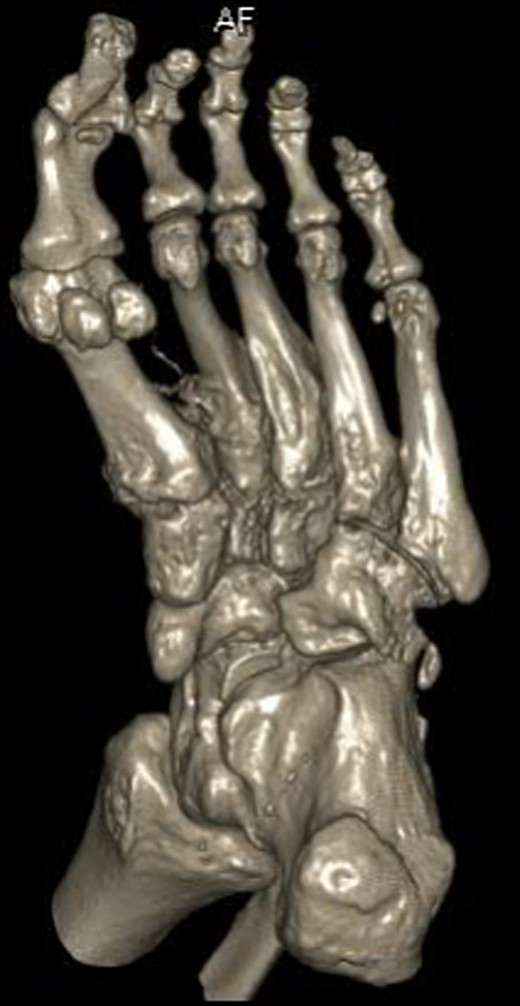

Dorsoplanter, lateral and oblique radiographs demonstrated an additional bone immediately distal to the middle cuneiform articulating with the second metatarsal base and middle cuneiform. Second and third metatarsals were shorßt in comparison with normal (Figs 1–3). Osteoarthritis was seen in all TMTJs and the first MTPJ. A computed tomography (CT) scan confirmed the presence of the additional bone and degenerative joint disease (Figs 4 and 5).

Three-dimensional CT reconstruction of the left foot in the dorsoplanter orientation.

The additional bone of this patients foot appears to exist as a completely separate entity to the regular middle cuneiform proximally and the second metatarsal distally. It has developed the characteristic cuneiform wedge shape and size and articulates with the second metatarsal. Given the clinical and radiological conclusions, this extra ossicle represents an interesting finding of a potential additional middle cuneiform.